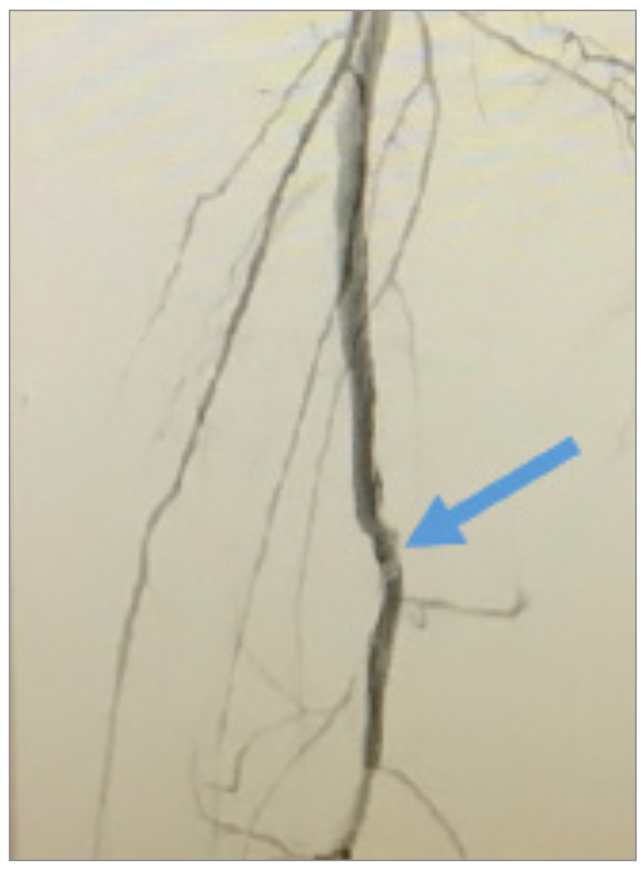

Internal tamponade of the left SFA access site was performed using a 4 × 150 cm Advance PTA balloon (Cook Medical) for 180 seconds, while removing the direct SFA access and Astato wire (Figure 5). We then turned our attention to the mid-SFA occlusion. An 18 g Victory wire (Boston Scientific) was used to cross the lesion, followed by a 3 × 40 mm, .014-inch LP balloon (Cook Medical), followed by a 5 × 200 mm Armada balloon (Abbott) to dilate the lesion (Figure 6). A dissection occurred in the SFA and popliteal arteries (Figure 7), so we placed a 6 × 250 mm Viabahn covered stent (Gore Medical) from the ostium to the distal SFA, and a 6 × 100 mm Zilver PTX stent (Cook Medical) was placed distal to the Viabahn covered stent, resulting in <10% residual stenosis and successfully tacking up the dissection (Figure 8). We then addressed the 99% distal popliteal/tibioperoneal (TP) trunk stenosis (Figure 9). We performed PTA of the TP trunk stenosis with a 4 × 28 mm Coronary Trek Balloon (Abbott), bringing the 99% stenosis to <20% residual stenosis (Figure 10) and improving the two-vessel flow to the foot (Figure 11).